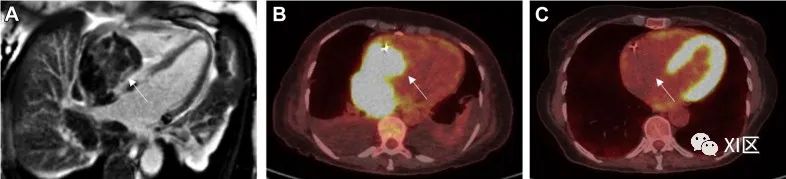

心脏副神经节瘤(图 6)是一种异常罕见的肿瘤,起源于与大动脉、冠状动脉或心房有关的副神经节细胞。它通常位于左心房(55%),其次是房间隔(16%)和心脏前表面(10%)。它们可以是分泌性肿瘤,也可以是非分泌性肿瘤。前者会产生内源性儿茶酚胺,导致交感神经过度放电,从而引起一系列症状(如心悸、潮红和震颤)。与其他心脏肿瘤一样,患者也可能出现呼吸困难和心绞痛症状,这与心腔或冠状动脉受压有关。

图 6 心脏副神经节瘤72 岁男性,心脏副神经节瘤,表现为潮红和心悸。(A)心脏 CT 显示,右心房上隔侧有一圆形异型肿块,造影剂摄取(白色箭头),右上肺静脉明显受压。肿块血管丰富,由右冠状动脉分支供应。(B)CMR(白色箭头)上的 SSFP 成像出现异质性。(C) 氟脱氧葡萄糖正电子发射断层扫描(FDG-PET)CT 上的右心房肿块(白色箭头)。

在超声心动图上,副神经节瘤通常表现为具有宽基底的回声性肿块。在心脏 CT 上,副神经节瘤表现为异质肿块,在平扫中呈低密度,在增强成像中呈明显强化。在 CMR 上,它们通常在 T2 加权图像上显示高信号强度(50)。正电子发射计算机断层成像(PET)预计也会呈阳性。明确诊断仍需组织病理学检查。